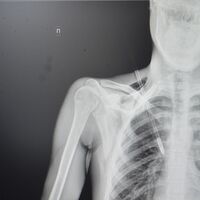

Как рассказали медики, юноша поступил в больницу на скорой со стрелой в грудной клетке. Он рассказал, что вместе с девушкой занимался стрельбой из спортивного лука, когда стрела срикошетила от дерева и вонзилась ему в грудь.

После госпитализации пациента отправили на экстренную операцию: стрела прошла между ключицей и правым ребром, пробив верхушку легкого на шесть сантиметров. По словам врачей, юноше повезло, что предмет не задел подключичную артерию или вену.

«Это привело бы к критическому кровотечению. Такие травмы требуют немедленного хирургического вмешательства. Мы успешно удалили инородное тело, а потом ушили поврежденное легкое и дренировали плевральную полость», — рассказал хирург больницы Тимур Колесников.